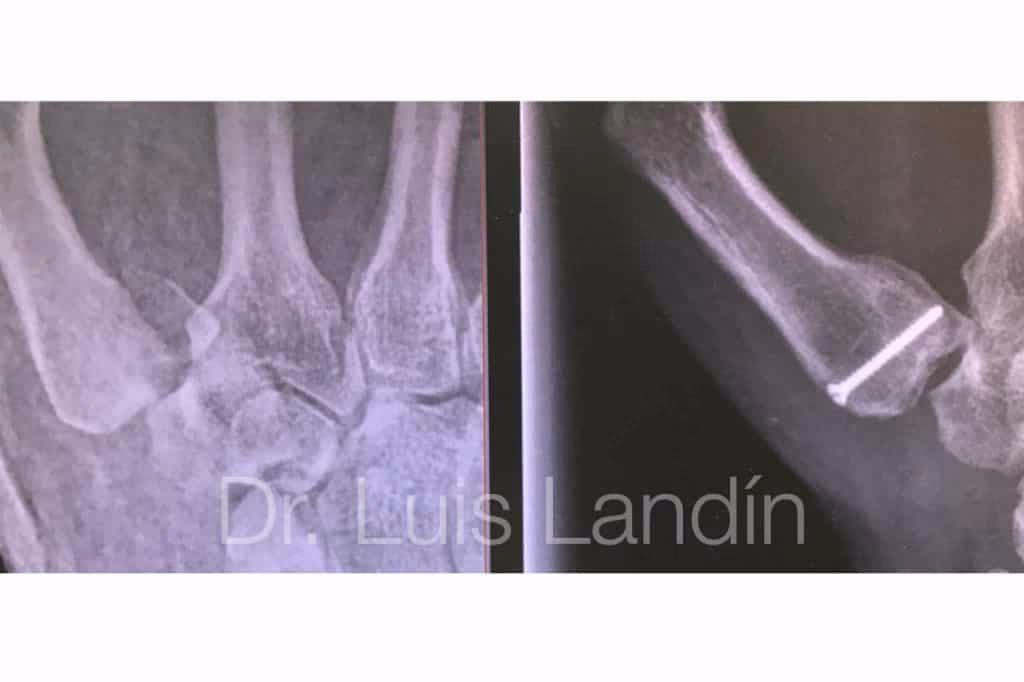

El diagnóstico de una fractura de Bennett generalmente se realiza mediante radiografías simples de la mano y el pulgar en diferentes proyecciones. Estas imágenes suelen ser suficientes para visualizar la fractura oblicua en la base del primer metacarpiano y la dislocación asociada de la articulación CMC. En la radiografía, se observa un pequeño fragmento triangular de hueso que permanece unido al ligamento oblicuo volar y que, debido a la acción de este ligamento y de los músculos, tiende a mantenerse en su posición anatómica respecto al trapecio, mientras que el resto del metacarpiano se desplaza proximal, dorsal y radialmente por la acción de los músculos abductor largo y extensor corto del pulgar.

Este método es el más común para fracturas de Bennett desplazadas, pero que aún son reducibles mediante manipulación externa. Se realiza la reducción cerrada como se describió anteriormente y, una vez que los fragmentos están alineados, se insertan percutáneamente (a través de la piel, sin abrir la articulación) una o dos agujas de Kirschner finas. Una aguja suele dirigirse desde la base del metacarpiano hacia el fragmento pequeño para fijarlo en su posición. Otra aguja puede usarse para estabilizar el metacarpiano principal, fijándolo al hueso trapecio o al segundo metacarpiano adyacente para evitar su desplazamiento.

Las agujas sobresalen de la piel y se cubren para evitar infecciones. Se mantiene una inmovilización con férula o yeso durante el tiempo que las agujas permanecen en su lugar, que suele ser de aproximadamente 4 semanas. Pasado este tiempo, se retiran las agujas en consulta y se inicia el programa de rehabilitación. Este método ofrece una mayor estabilidad que el yeso solo, pero aún presenta un riesgo de desplazamiento si la fijación no es lo suficientemente sólida o si el paciente no sigue las precauciones.

Este enfoque quirúrgico se reserva generalmente para fracturas de Bennett con un desplazamiento significativo (típicamente > 3 mm), cuando la fractura no puede ser reducida de forma cerrada, o si hay un fragmento articular grande e inestable. La técnica implica realizar una incisión quirúrgica para exponer la articulación y la fractura bajo visión directa. Los fragmentos óseos se manipulan y se alinean de forma precisa (reducción anatómica) y luego se fijan internamente. La fijación puede realizarse con agujas de Kirschner, tornillos pequeños o, en casos complejos, miniplacas y tornillos. La elección del implante depende del tamaño y patrón de la fractura.